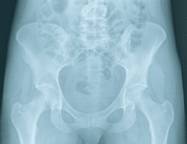

Chez les femmes, la décroissance de la masse osseuse débute quelques années avant la ménopause. La perte osseuse est alors de l'ordre de 1 à 2 % par an, pendant 8 à 10 ans, mais elle peut être plus considérable (5% par an). Passée cette période, la perte osseuse se stabilise autour de l'ordre de 0,5 - 1 % par an ; les rythmes de décroissance osseuse deviennent comparables chez l'homme et la femme. L'os spongieux est le premier touché par l'ostéoporose. Cet os se trouve en particulier au niveau des vertèbres. Lorsque la maladie évolue, les os longs s'amincissent dans leur partie externe, au niveau où l'os compact est plus présent. C'est pourquoi il existe des risques de fracture du col du fémur. L'ensemble du squelette peut être touché par l'ostéoporose, mais certains os sont plus vulnérables. Les conséquences de l'ostéoporose se font surtout sentir pour les os suivants : les vertèbres, les os du poignet, le col du fémur et les os de la mâchoire.

Les fractures du col du fémur. Elles ont lieu souvent après 75 ans et peuvent affecter l'autonomie de la personne âgée. La fracture du col du fémur peut être dramatique et causer le décès du patient dans l'année suivant l'accident (20 % des cas environ).